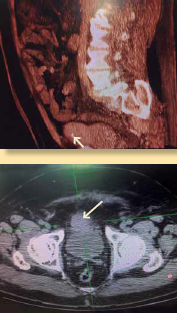

Masculino de 67 años con diagnóstico de para ganglioma vesical. Detectado cuatro meses antes de su intervención por presencia de hematuria macroscópica, sin otros síntomas acompañantes (figuras 1a y 1b). Diabético de larga data con neuropatía periférica tratado con hipoglicemiantes orales y gabapentina. Hipertensión arterial tratada con ARAII (losartán) en aparente control. Fue hospitalizado para preparación y solicitado para cistectomía parcial más resección de tumoración. Valoración y ajuste de tratamiento por el servicio de endocrinología, sustituyendo antihipertensivo ARA II por alfa 1 antagonista (Prazosin 1 mg cada 12 horas), y esquema de insulina. Durante su valoración preanestésica, se encontró descontrol glucémico presentando glucosa de 280 miligramos por decilitro, con ajuste de tratamiento. Signos vitales dentro de parámetros aceptables. Clasificación de riesgo por estado físico ASA III.

Imágenes de los estudios: Cortesía del autor

Figura 1 a) Resonancia magnética y b) tomografía axial donde se observa la presencia de tumoración (paraganglioma) localizado en la vejiga.